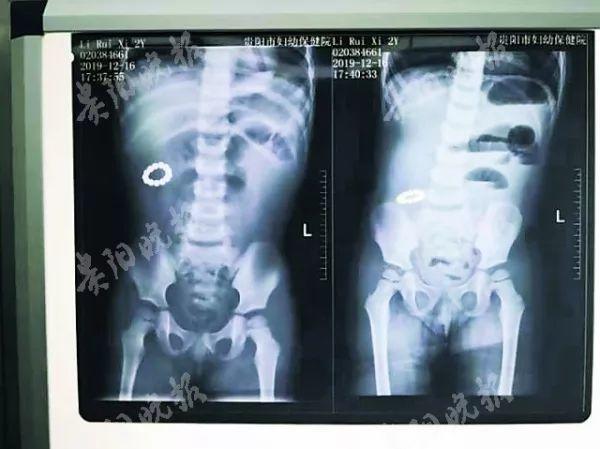

【两岁儿童误吞13颗磁力*珠钢**,13颗磁力*珠钢**黏附在孩子肠壁聚集成环状,导致肠道10处缺血坏死穿孔】

更让人触目惊心的是仅【浙江省质安院统计的 2019 年底- 2020 年初的数据,关于磁力珠的报道就高达 12 件】内容全是因孩子误食,导致肠穿孔的新闻,无一例外。